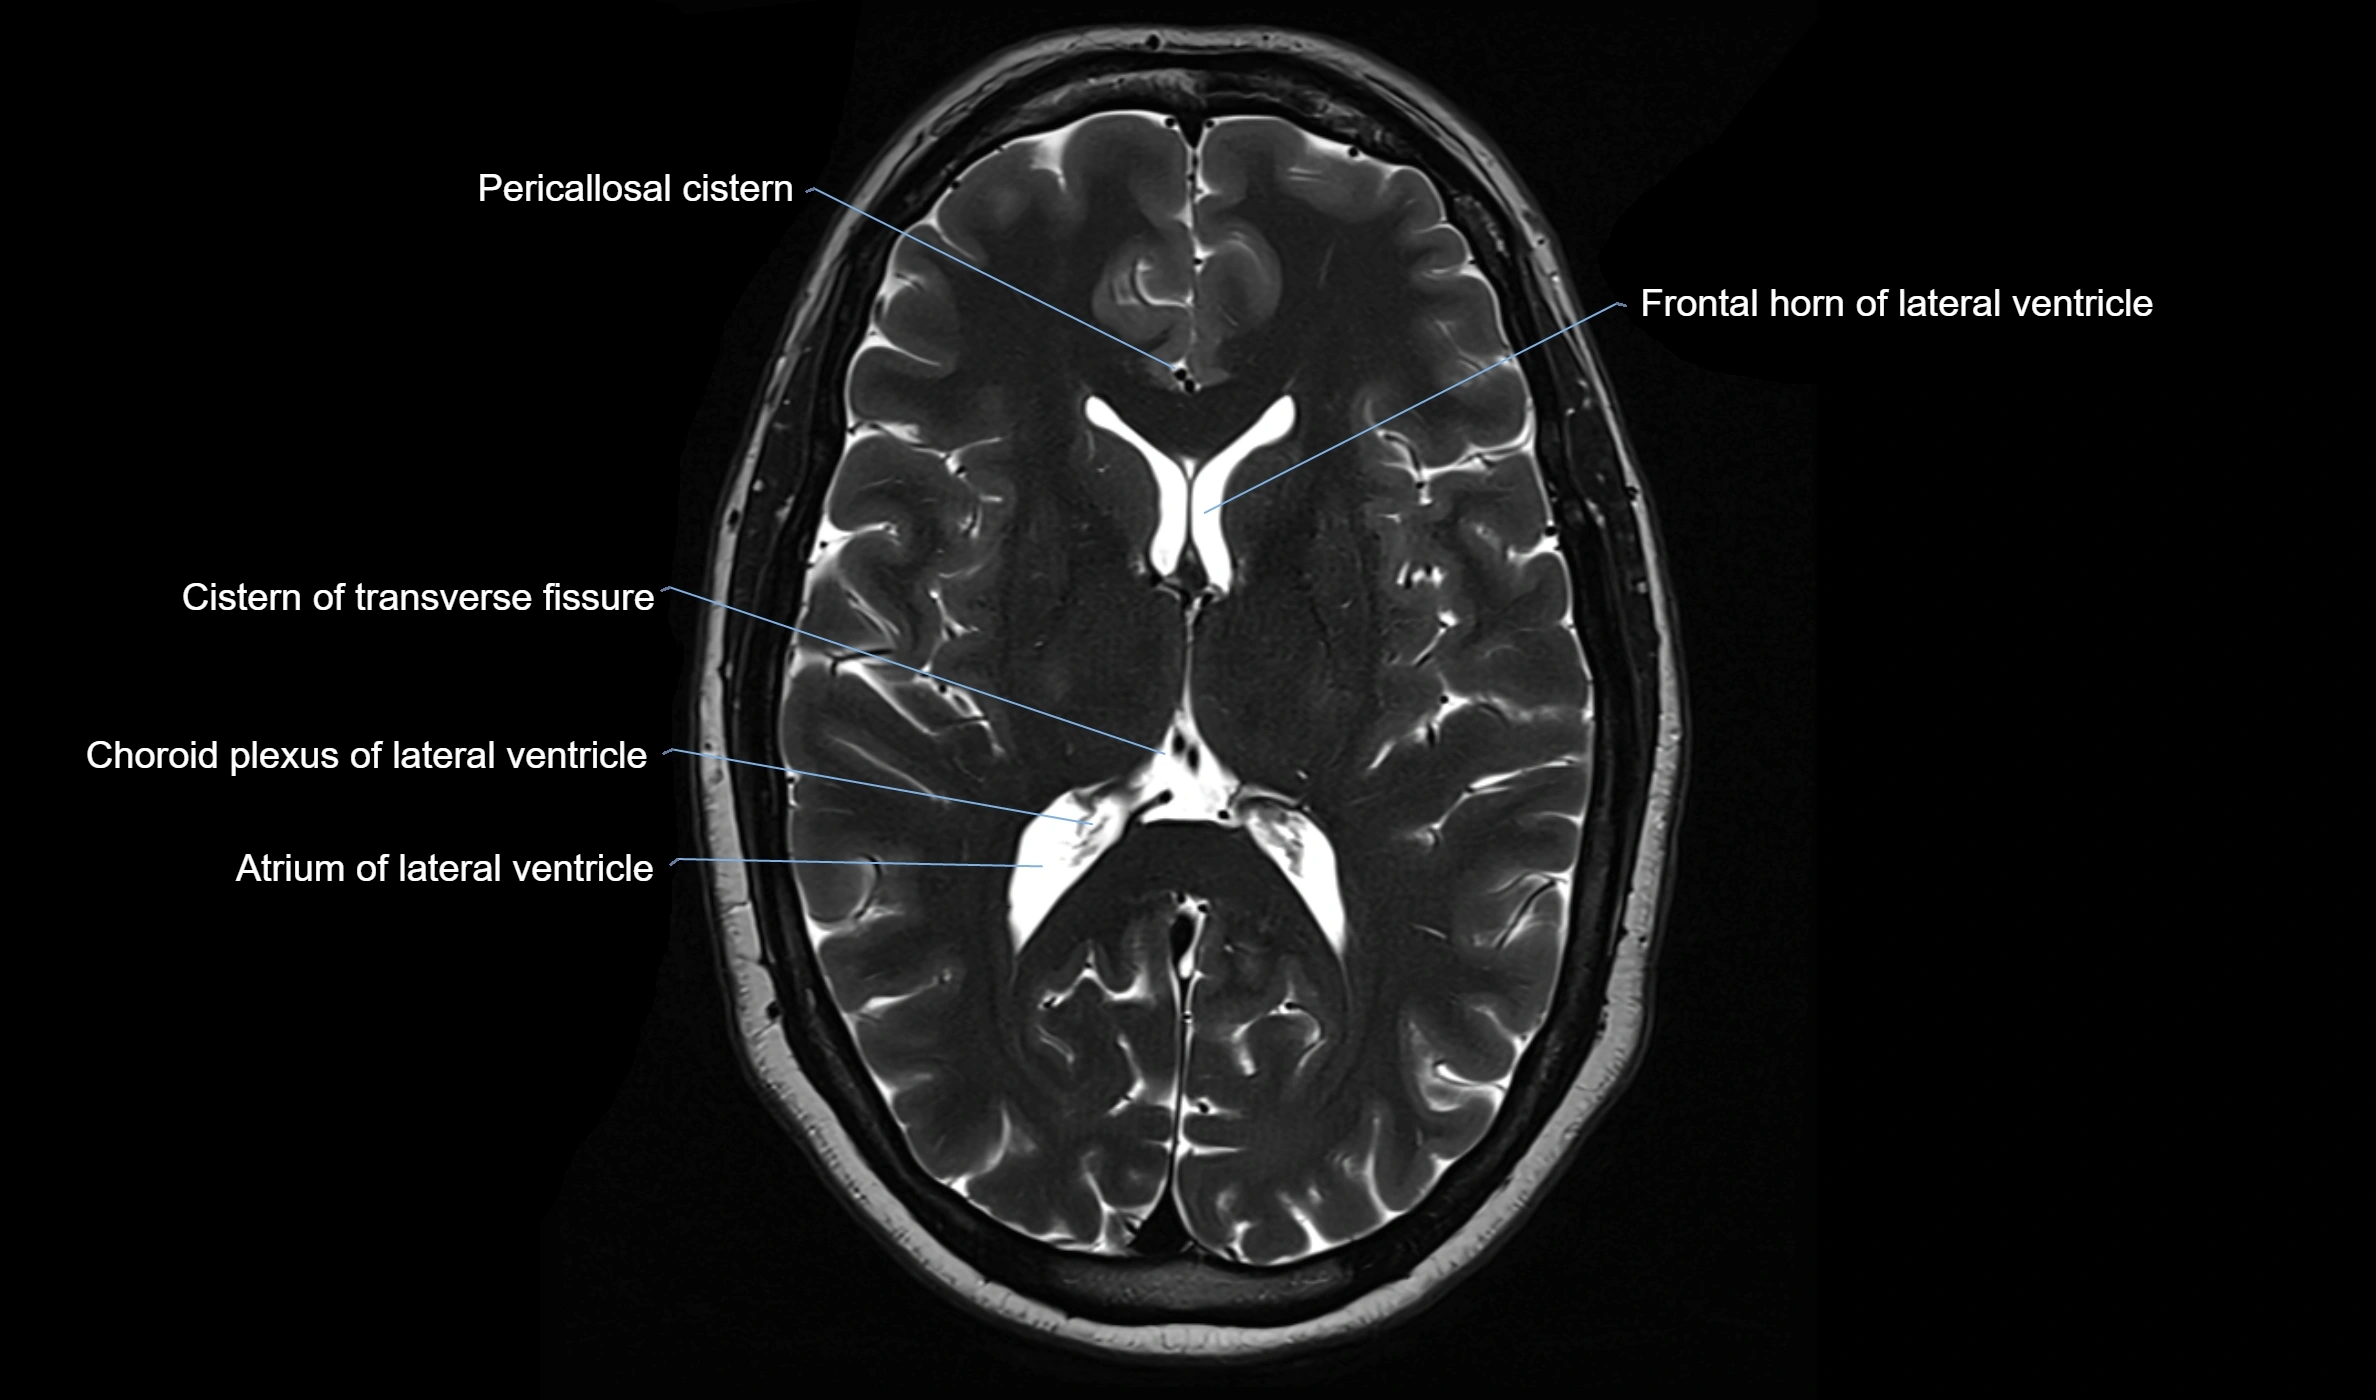

MRI images

image